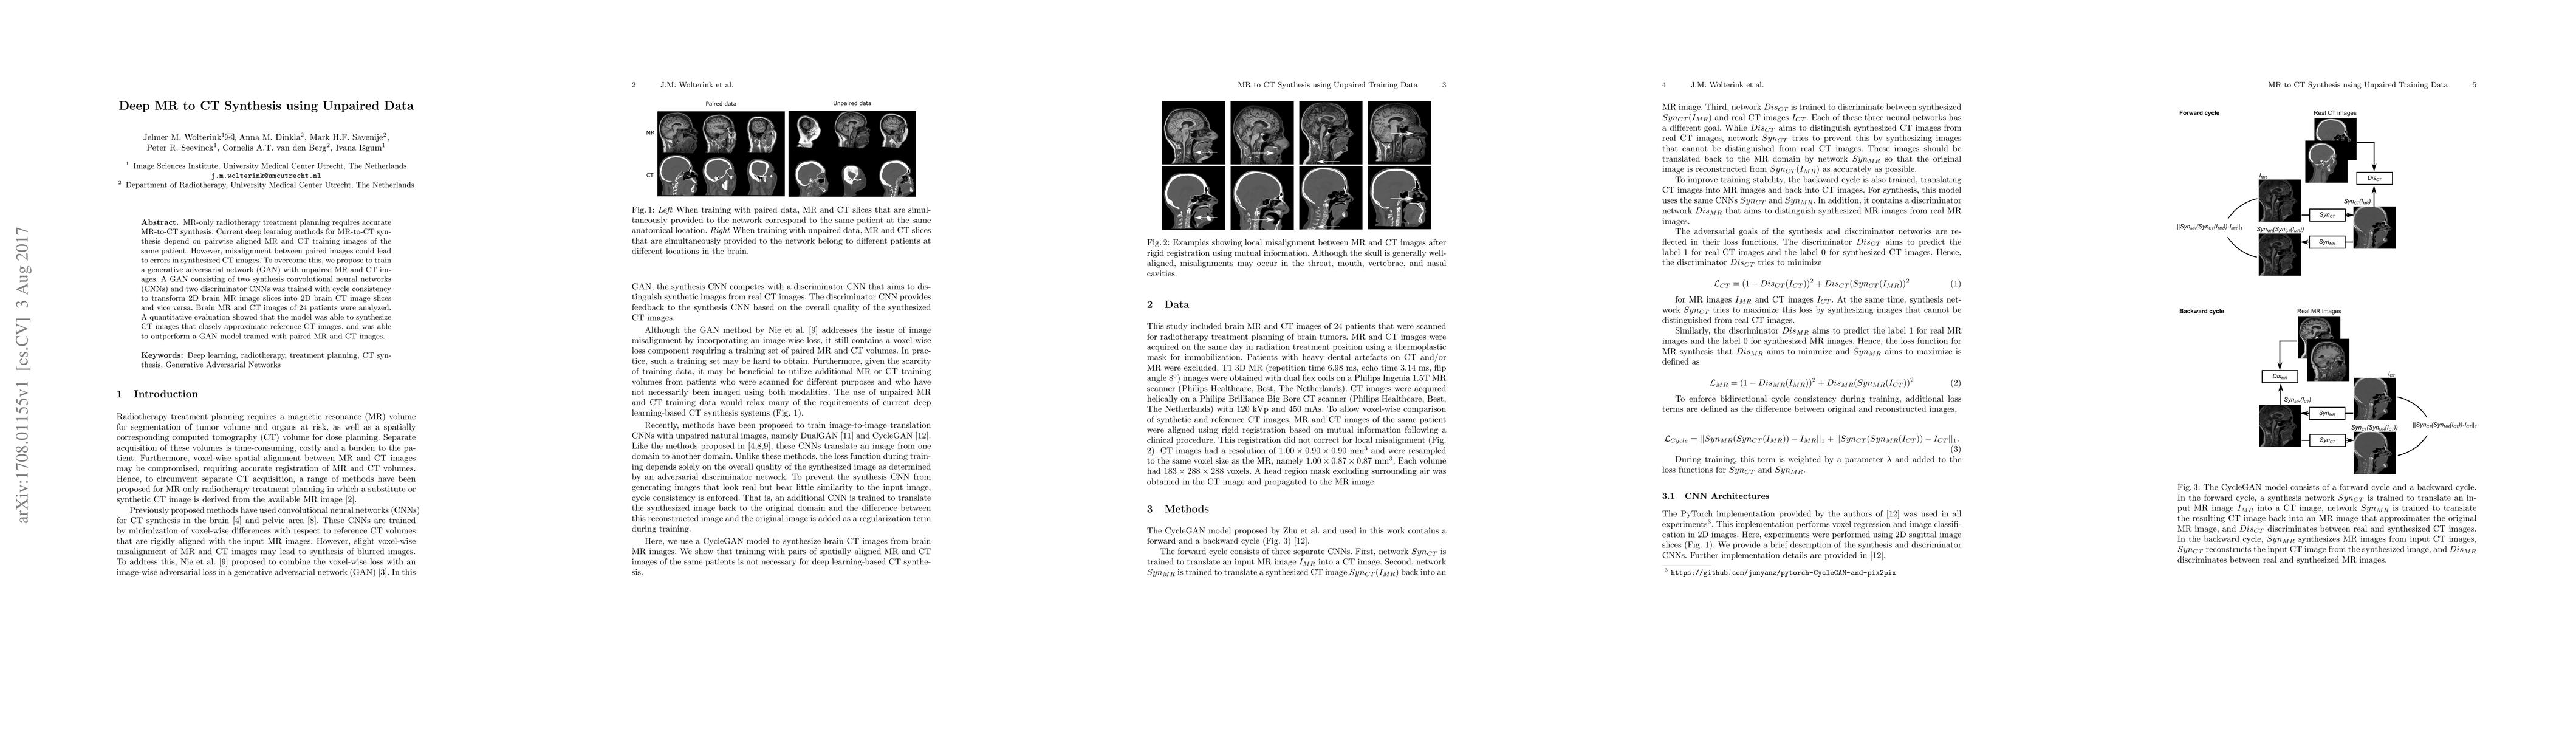

MR-only radiotherapy treatment planning requires accurate MR-to-CT synthesis. Current deep learning methods for MR-to-CT synthesis depend on pairwise aligned MR and CT training images of the same patient. However, misalignment between paired images could lead to errors in synthesized CT images. To overcome this, we propose to train a generative adversarial network (GAN) with unpaired MR and CT images. A GAN consisting of two synthesis convolutional neural networks (CNNs) and two discriminator CNNs was trained with cycle consistency to transform 2D brain MR image slices into 2D brain CT image slices and vice versa. Brain MR and CT images of 24 patients were analyzed. A quantitative evaluation showed that the model was able to synthesize CT images that closely approximate reference CT images, and was able to outperform a GAN model trained with paired MR and CT images.